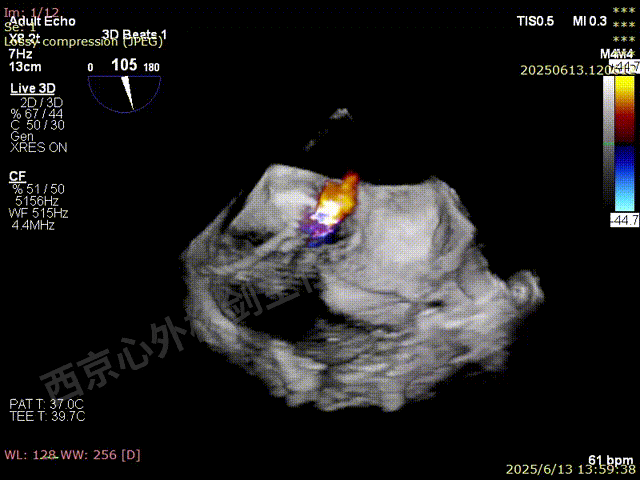

TEER术前超声评估

二尖瓣后叶栓系严重,前叶相对错位,反流束沿2区分布广泛,2偏3区处存在反流。

反流宽度至少23mm,因影像调整困难,考虑实际反流更宽。